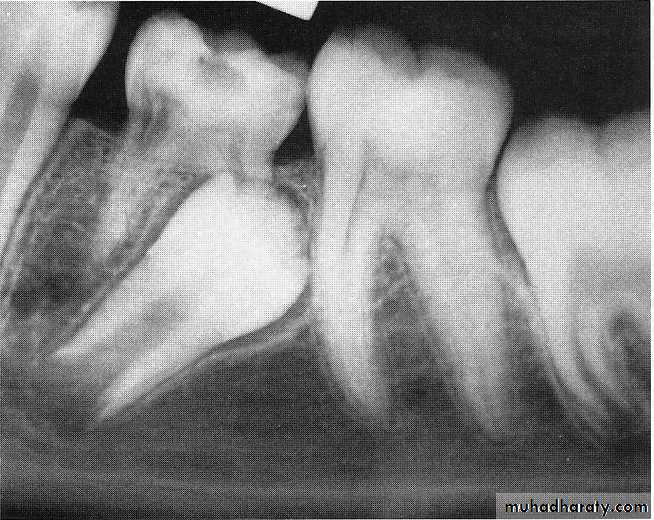

The diagnosis of an ankylosed tooth is not difficult to make.

1-Because eruption has not occurred and the alveolar process has not developed in normal occlusion, the opposing molars in the area seem to be out of occlusion.2-The ankylosed tooth is not mobile, even in cases of advanced root resorption.

3-The ankylosed tooth will have a solid sound, whereas the normal tooth will have a cushioned sound because it has an intact periodontal membrane that absorbs some of the shock of the blow.

The radiograph is often a valuable aid in making a diagnosis.

A break in the continuity of the periodontal membrane indicating an area of ankylosis is often evident radiographically.In the management of an ankylosed tooth, early recognition and diagnosis are extremely important.